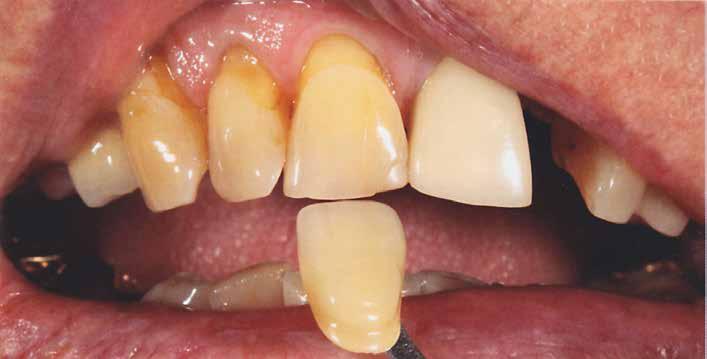

A cikkben egy fiatal nő kezelésének interdiszciplináris megközelítését foglaltuk össze, aki fogászati állapota miatt hoszszú ideje szenvedett fizikálisan és pszichésen is (1. ábra)

Amikor a 25 éves Andrea először konzultált a rendelővel, már több éve küszködött súlyos panaszokkal. Állapota két különböző betegségnek köszönhető, melyek egyrészt önmagukban, másrészt egymással kölcsönhatásban is súlyos következményekkel jártak. A fiatal nő veleszületett genetikai elváltozásban szenved, melynek tünete többek között a gyenge zománcfejlődés. Továbbá a beteget fibromyalgiával is diagnosztizálták, mely krónikus fájdalom rendellenesség, ami komoly tünetegyüttessel járó pszichés szorongás. A betegség egyik következménye az volt, hogy a páciens az elmúlt években átlagosan napi három-négyszer hányt. Az ebből fakadó savas erózió a már amúgy is veszélyben lévő fogazatot tovább roncsolta (2. ábra)

A páciens elviselhetetlen fájdalmakról számolt be, beleértve a többszörös szájüregi fertőzéseket is. Az elmúlt években az előírt számos antibiotikumos kezelés egyre gyengébb hatásfokkal működött. A fertőzések következtében több fogát is extrahálni kellett. A fogászati állapotával együtt az étkezés minősége is romlott. A súlyos esztétikai korlátok is terhet jelentettek. A psziché és az önbizalom komoly károkat szenvedett. Fogorvosnál tett korábbi látogatásai kellemetlen élményt jelentettek. Emiatt kezdetben vonakodott beleegyezni a komplex terápiába. Empatikus, érzékeny beszélgetések folyamán körvonalazódott számára a kezelés fontossága.